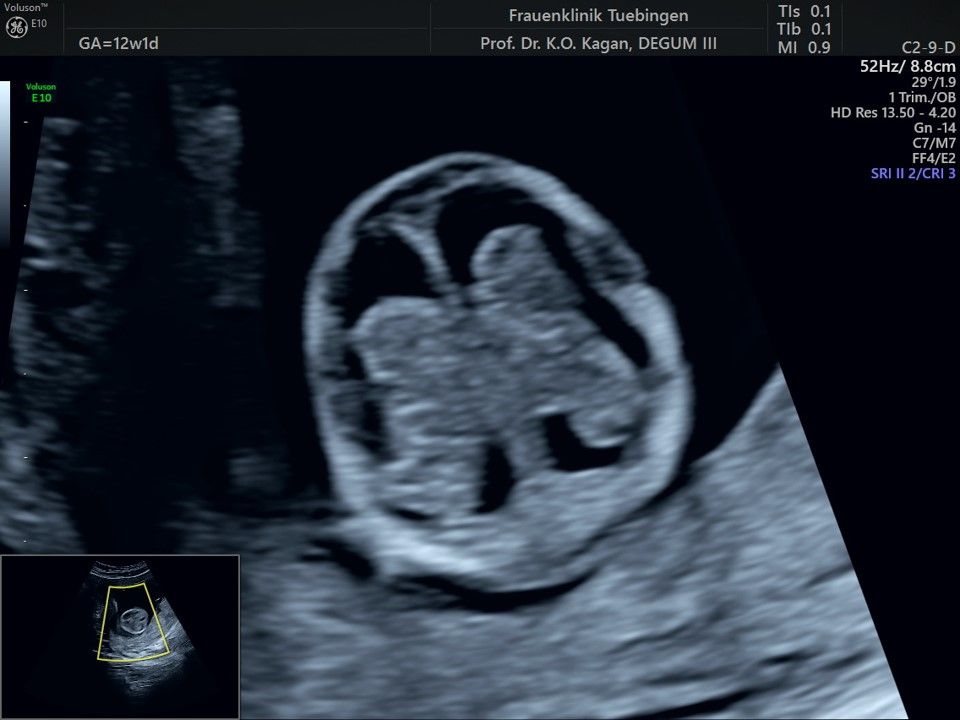

Im Rahmen des Ersttrimester-Screenings untersuchen wir die Organe des Feten mittels Ultraschall. Dabei machen wir auch gerne ein Bild für Sie.

Obwohl der Fet zu diesem Zeitpunkt erst zwischen 5 und 8cm groß ist, lassen sich bereits etwa die Hälfte aller schwerwiegenden Fehlbildungen erkennen bzw. ausschließen. Sollten wir eine Auffälligkeit sehen, werden wir mit Ihnen den Befund und das weitere Vorgehen ausführlich besprechen.

Fetale Anatomie

Herz

Bauchwanddefekt